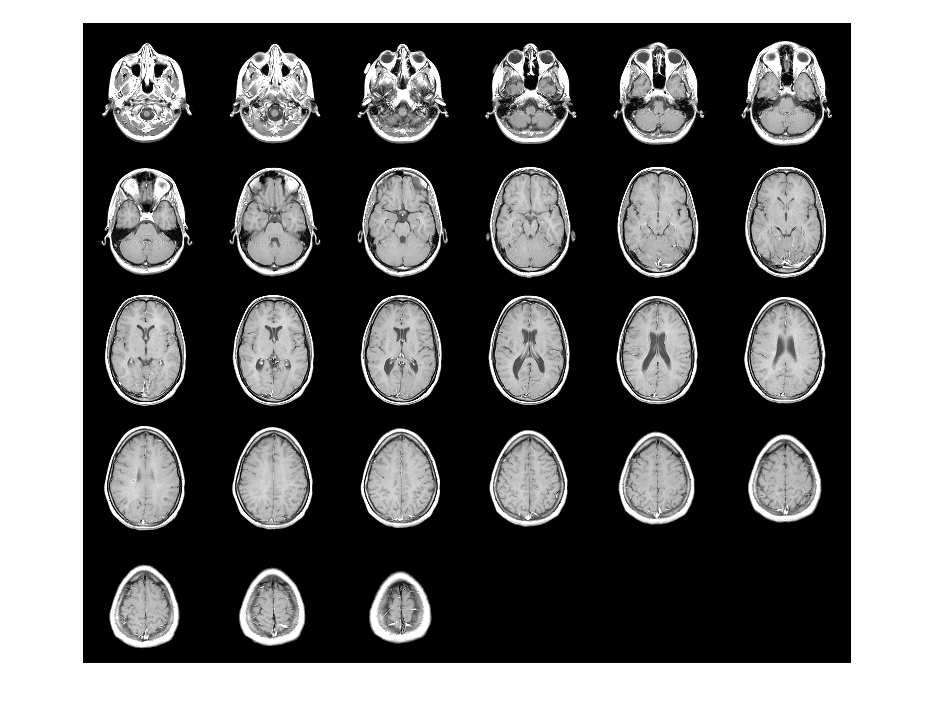

imtile

Combine multiple image frames into one rectangular tiled image

returns a tiled image containing the images in the files with file names

out = imtile(filenames)filenames.

By default, the imtile function arranges the images so that they

roughly form a square. You can change the arrangement using optional name-value arguments.